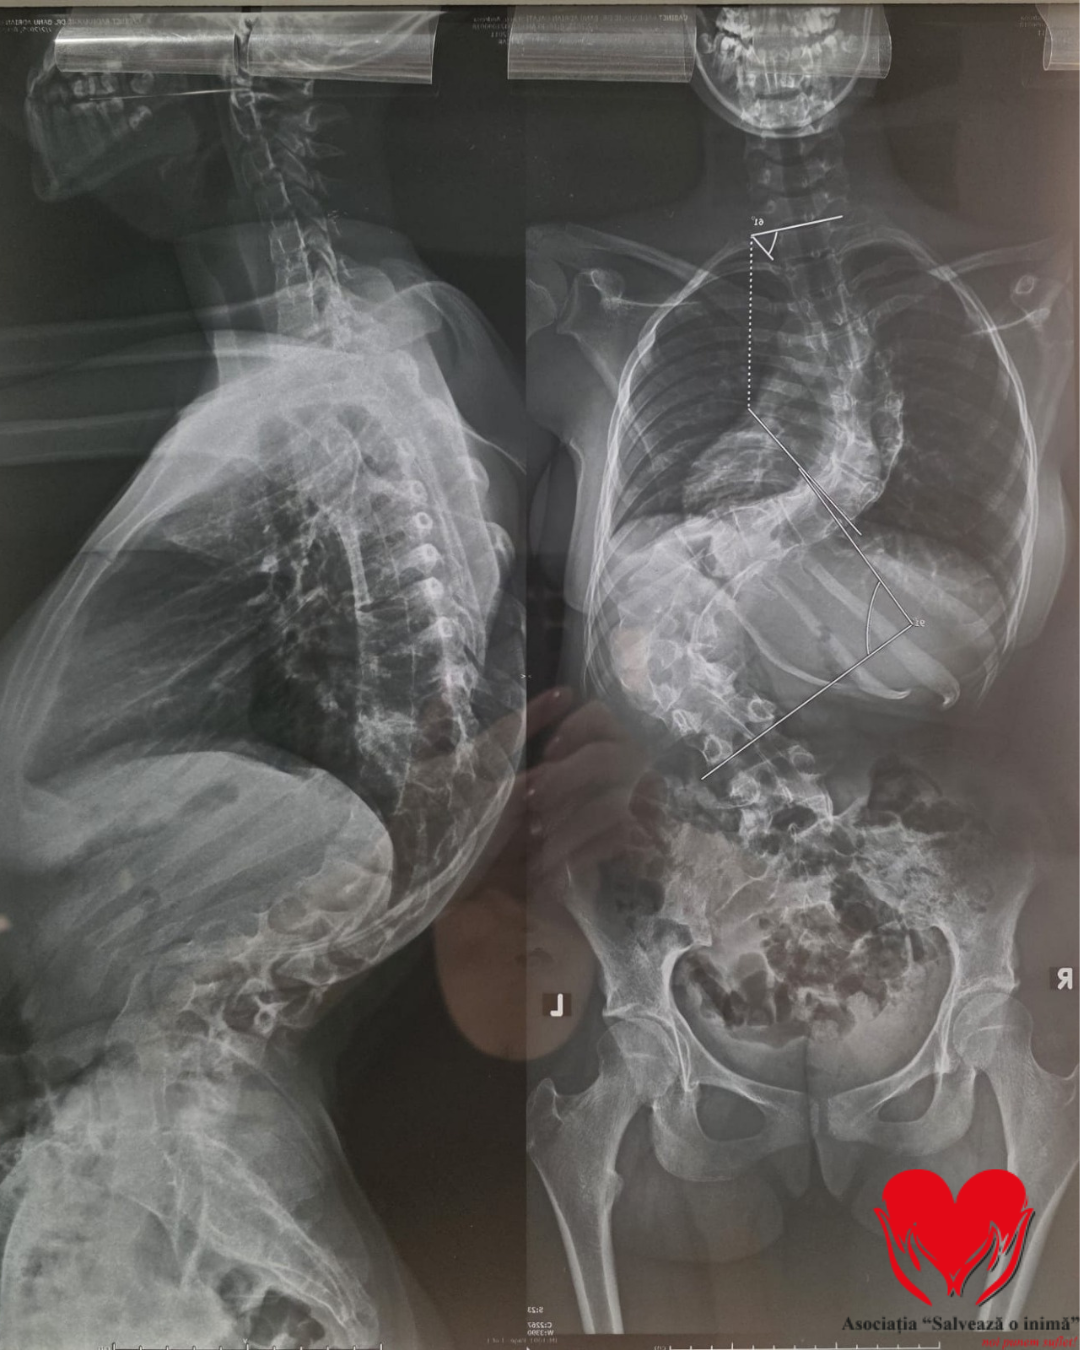

În prezent, medicii vorbesc despre o formă gravă a afecțiunii, cu o curbură de 31 de grade lombar și 61 de grade toracic, valori extrem de periculoase pentru un copil aflat în plină dezvoltare.

Specialiștii avertizează că, fără o intervenție chirurgicală rapidă, coloana vertebrală poate comprima organe vitale, în special plămânii și inima, cu riscul apariției insuficienței respiratorii, pierderii mobilității și al unor limitări majore pe termen lung.